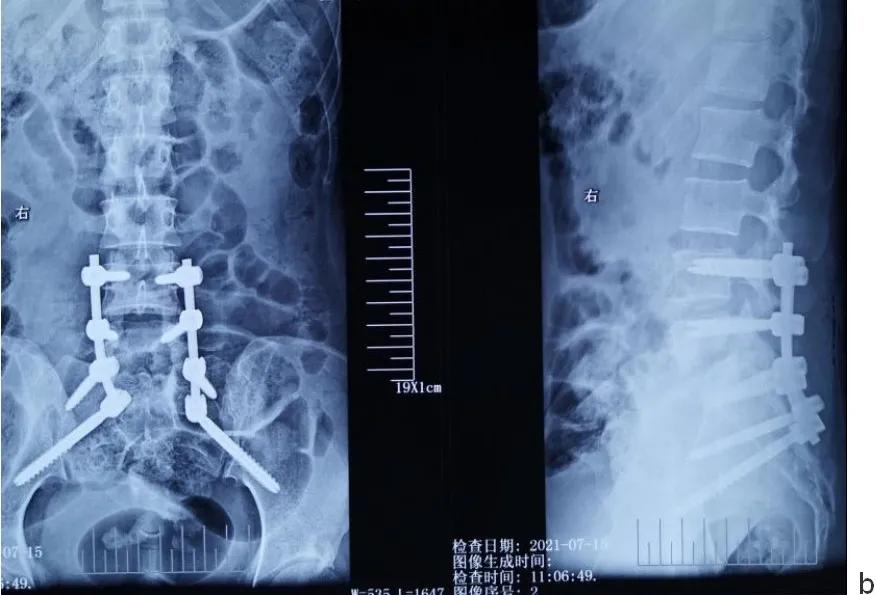

术后影像学检查

a.术后髂翼位置示双侧S2AI钉位置良好。

b.术后正侧位片示腰4/5/骶1螺钉位置良好。

c.前路植骨术后正侧位片示腰4/5/骶1螺钉位置良好,腰5-骶1椎间植骨(自体髂骨三层皮质骨)位置良好。